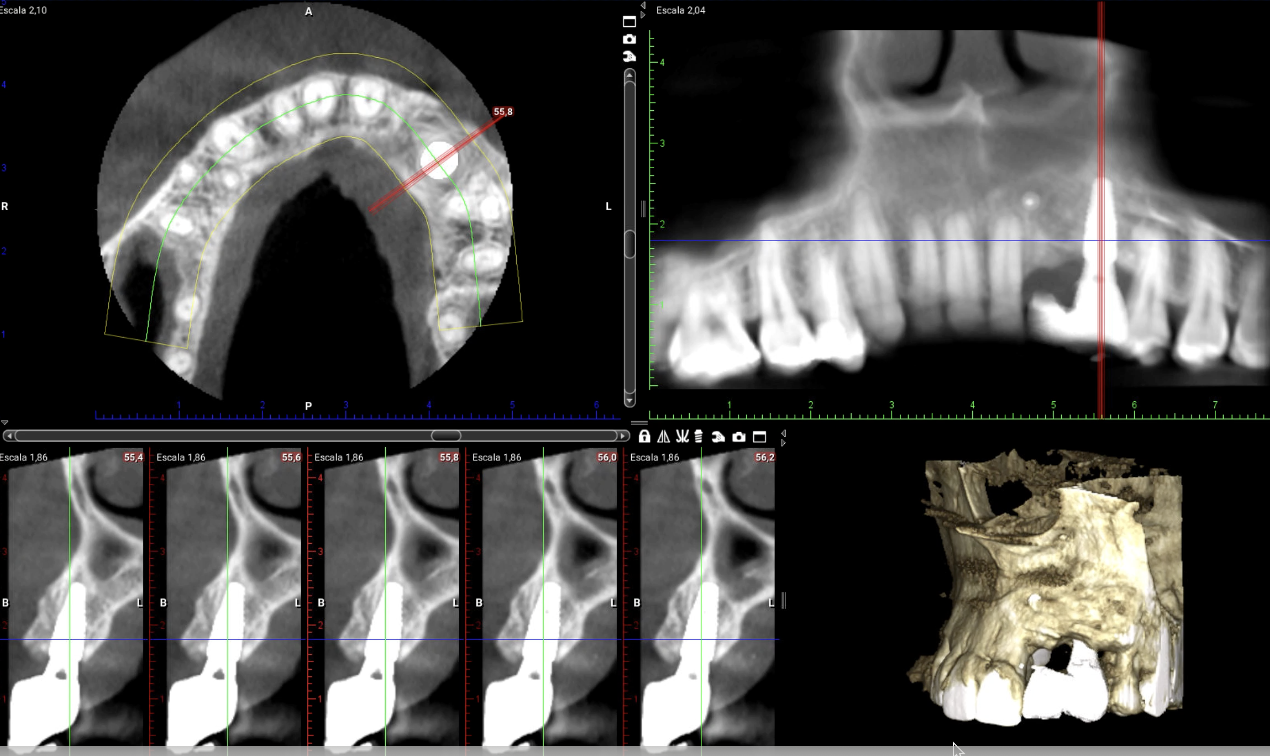

3D guided bone regeneration using an e-PTFE, Ti-reinforced NeoGen® membrane and 100% autogenous bone is a fully predictable treatment for the severe hard and soft tissue atrophy on the Aesthetic Zone. This statement is supported not only by panoramic and periapical x-rays, but also by CBCT sectional cuts where we can see the complete stability of the regenerated bone.